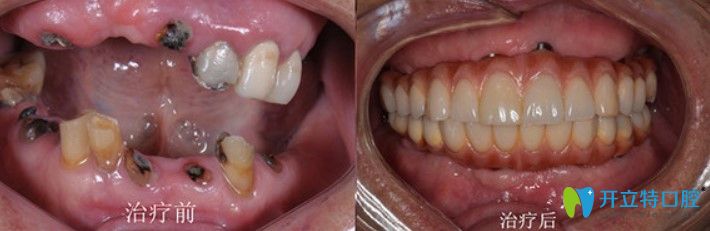

張大爺,69歲

牙齒情況:上半口牙齒脫落

種植方式:微創(chuàng)即刻種植技術(shù)

諾德齒科半口種植牙案例圖